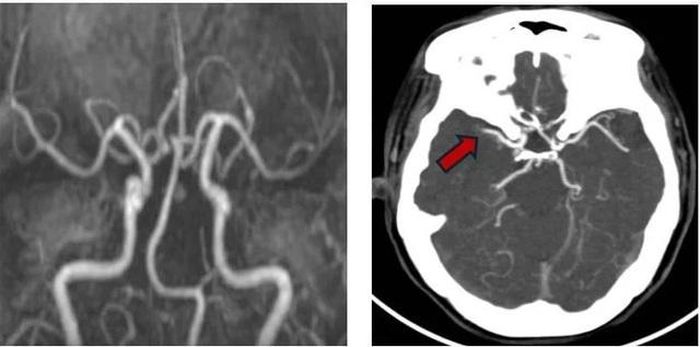

Hình ảnh mạch máu đã tái thông trước đó với thuốc tiệu sợi huyết (Hình A) và tái tắc do huyết khối mới – Rung nhĩ (Hình B – mũi tên đỏ). Ảnh: BVCC

Lập tức, các bác sĩ tại Khoa Bệnh lý mạch máu não kích hoạt quy trình báo động đột quỵ nội viện. Chụp CT mạch máu não khẩn ghi nhận hình ảnh tắc động mạch não giữa bên phải – với hình ảnh huyết khối mới hình thành trong lòng mạch máu. Không để thời gian trôi qua vô ích, người bệnh được chuyển thẳng vào đơn vị can thiệp mạch máu thần kinh. Tại đây, quy trình can thiệp nội mạch được thực hiện khẩn trương và chính xác.